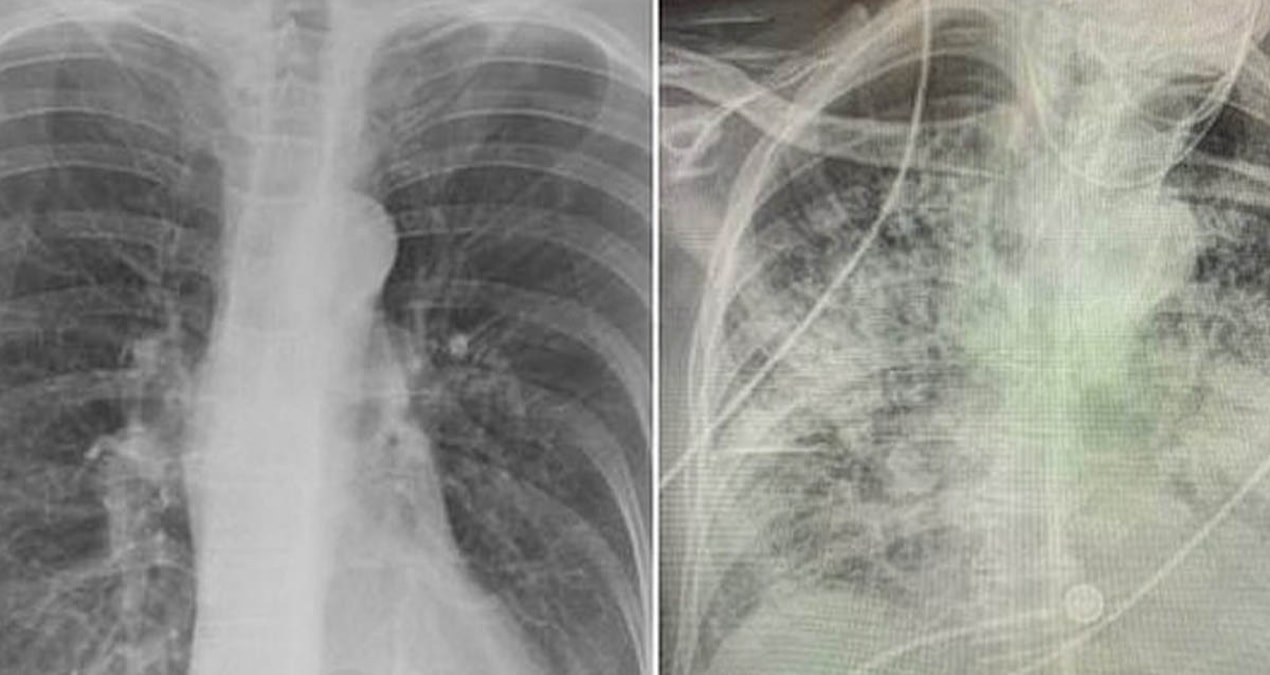

Akciğerler, sigaranın etkilerinin en belirgin görüldüğü organdır; sigara içmek akciğerlerin görünümünü değiştirir, kararmasına, elastikiyet kaybına ve iltihaplanmasına neden olur.